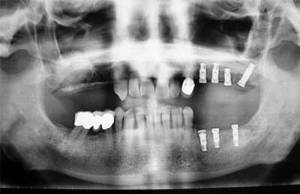

La incorporación de la implantología en la práctica odontológica ha representado un gran avance para la rehabilitación-restauración de la perdida de los dientes. Antes se instalaban prótesis apoyadas en otros dientes o sobre la mucosa bucal produciéndose todo tipo de complicaciones. Los implantes dentarios son fijaciones (tornillos) de titanio con superficies bioactivas que se colocan en los maxilares (intraóseos), imitando una raíz dentaria aunque su comportamiento es diferente.

El diagnóstico en implantología es complejo, puesto que exige una buena coordinación entre el cirujano y el protesista. Normalmente se precisan estudios radiográficos especiales (tomografía computadorizada o escáner), encerados diagnósticos, preparación de férulas quirúrgicas, etc. para minimizar los riesgos asociados a un acto quirúrgico irreversible.

El plan de tratamiento implantológico debe adaptarse a cada caso concreto ya que depende de muchos factores: del tipo de edentulismo (cuantos dientes faltan) , de la calidad y cantidad de hueso maxilar disponible, del tipo de oclusión, del estado periodontal de los dientes que permanecen en boca, de las parafunciones como el apretamiento dentario (bruxismo), del estado de salud general del paciente, etc.

Las fijaciones o implantes se pueden instalar en el hueso alveolar de forma inmediata (tras la extracción del diente) o de forma diferida (al cabo de unos meses cuando la mucosa y el hueso este cicatrizado). Igualmente la prótesis puede colocarse de forma inmediata (es una prótesis provisional y normalmente fuera de oclusión) o de forma diferida (cuando el implante esta osteointegrado: 2-4 meses en la mandíbula y de 4 a 6 meses en el maxilar superior).

Una de las técnicas más modernas es la colocación de implantes con cirugía guiada y con mínimas incisiones. Se precisa planificar la intervención quirúrgica con un férula quirúrgica preparada tras un estudio radiográfico completo (tomografía computadorizada o escáner).